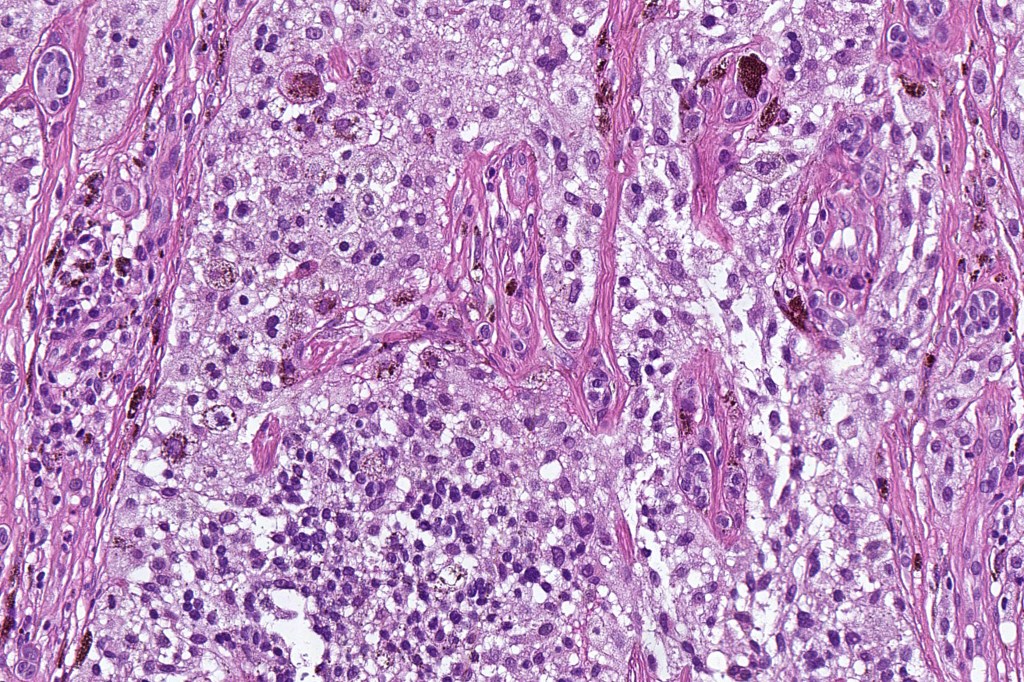

•May affect the tumor in part or whole

•Enlarged cells with copious eosinophilic, foamy or clear cytoplasm (some authors include melanoma with clear cell change in the same category)

•Variable pigmentation

•Nuclei vesicular or hyperchromatic

•Pleomorphism is not generally marked and indeed can be very subtle

•Variable mitotic activity

•DPAS granules

•Thought to be a result of abnormal or degenerative melanosome change